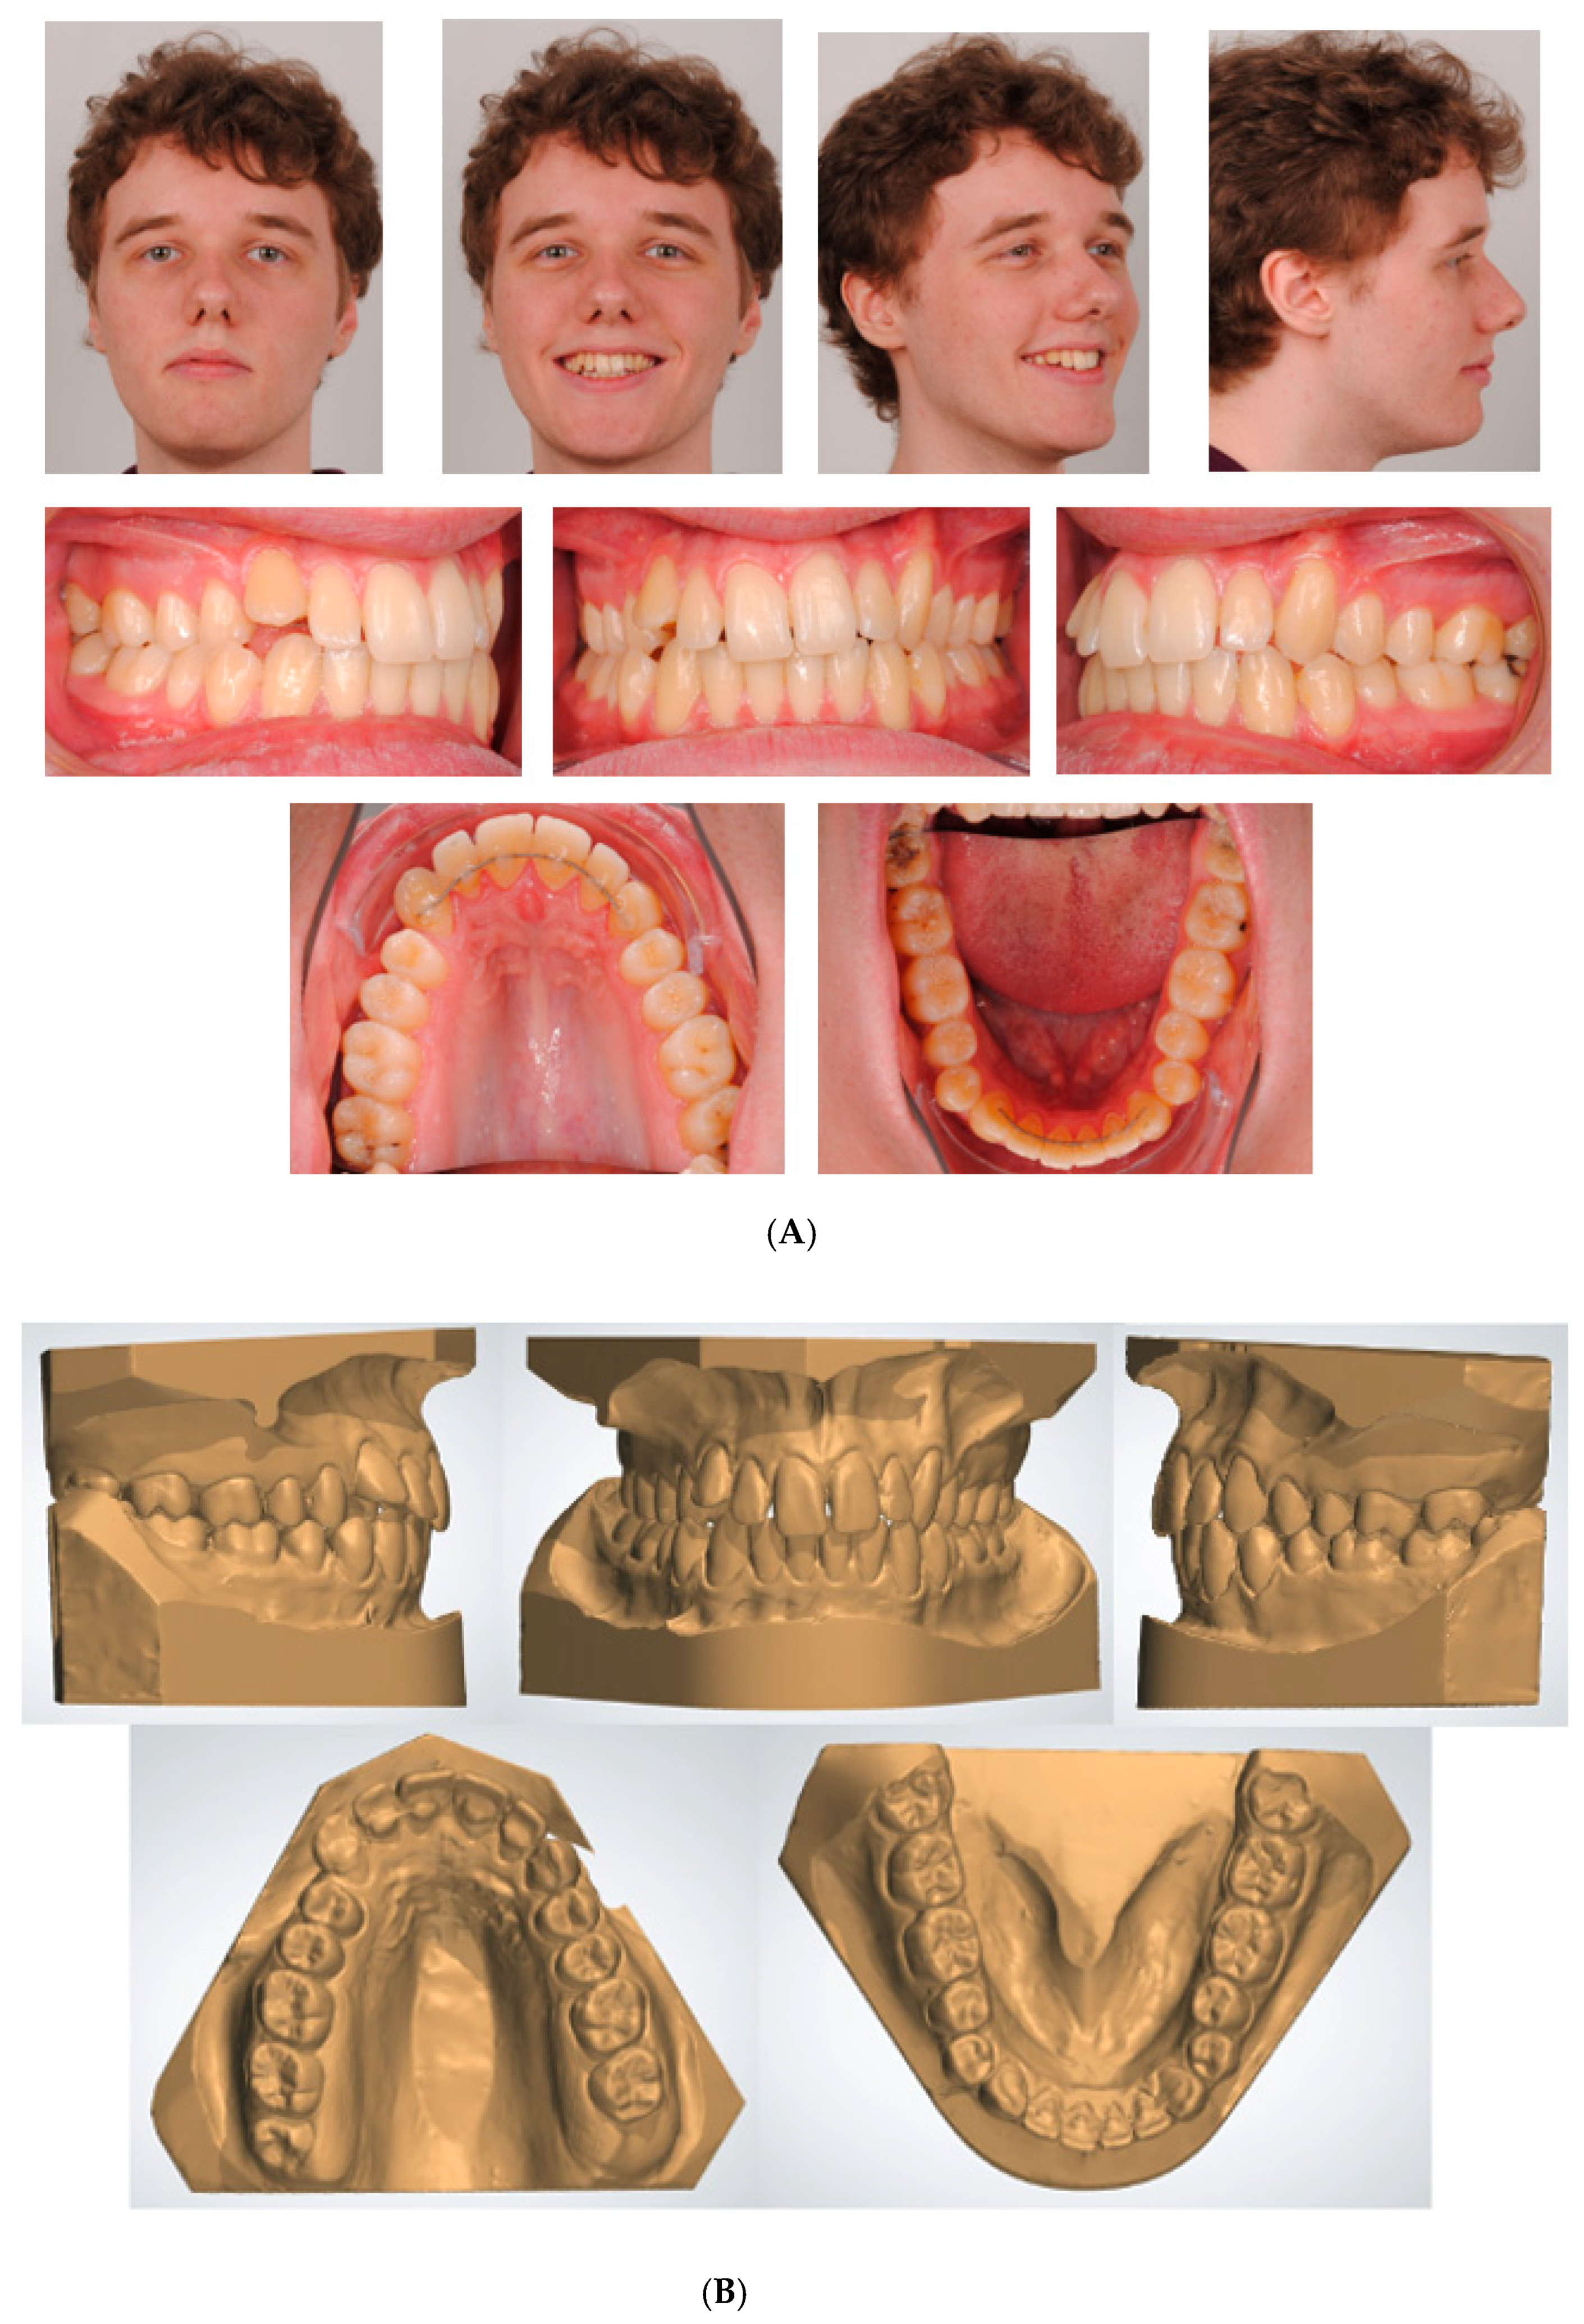

3.1.1. Clinician- and Patient-Assessed Outcomes

The end result of the orthodontic re-treatment is shown in Figure 5. The cant of the upper incisors, the excessive palatal and buccal root torque of the 13 and 23, and the crossbites were corrected. In addition to aesthetic improvement, cuspid guidance on the left and right sides was achieved. However, the panoramic radiograph showed an increase in root resorption (Figure 4), and a buccal gingival recession was observed at the 23 (Figure 5). To assess the outcome of this orthodontic re-treatment, the Peer Assessment Rating (PAR) index was consulted and resulted in a PAR score of 2 [22]. Compared to the PAR score measured before the orthodontic re-treatment (PAR score of 12), the malocclusion improved by 83% (10/12). The patient participated in the ESAS patient satisfaction evaluation questionnaire to assess the outcome of the orthodontic re-treatment. ESAS (EFOSA Self Assessment System) is a quality assessment system available to all orthodontists in Europe [27]. This patient satisfaction evaluation questionnaire rates different aspects of the treatment, e.g., patient satisfaction with the orthodontist, assistants, practice, and overall treatment. The completed questionnaire is provided (Supplementary File S3). The answers indicated that the patient was satisfied with nearly all aspects. Nevertheless, the treatment duration was slightly longer than expected, and he believed that the waiting room was not comfortable enough.

Figure 5. Extra-oral and intra-oral photographs after orthodontic re-treatment.